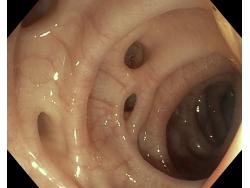

Uchyłki